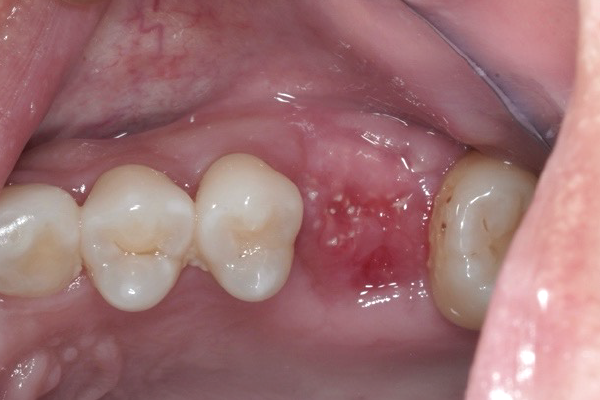

歯槽堤温存術(リッジプリザベーション)

後4週間

術後4週間のレントゲン写真

歯を抜歯し、骨補填剤をいれ、骨補填剤が出てこないようにメンブレンで閉じました。

大きな感染もなく歯肉の状態も良好です。

これから、5ヶ月前後治癒期間を待ちその後インプラント治療を行なっていきます。